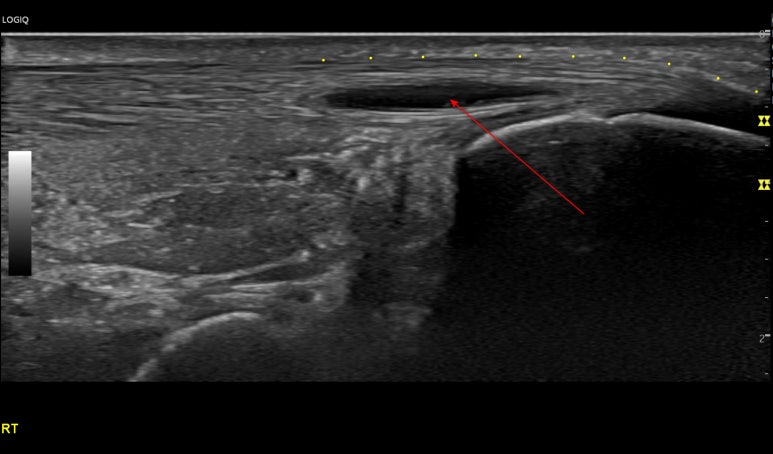

영상에서

족태양경근은 깊이에 따라

아킬레스건, 장무지굴근, 종골, 거골 등

다양한 구조물이 보입니다.

그 중에

아킬레스건(ACH T)은흰색 줄무늬 섬유 패턴으로보이는데요.

위 환자분은

아킬레스건이

많이 부어있으셨고요.

화살표친까만색 틈이 보이시나요?

정형외과에서

아킬레스건 염증이 심해지며

찢어지고 있다고

들으셨다고요.

힘줄이 완전히 파열되면

수술도 고려해봐야 됩니다.

일반적으로 한국인의 아킬레스건은

5mm를 넘지 않는데요.

이 환자분은9mm 정도가 나옵니다.2배 가까이부은 상태죠?

오랜 기간동안

만성 염증에 시달렸던 것을

알 수 있습니다.